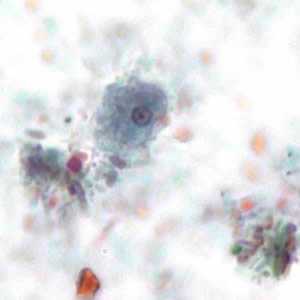

E. coli trophozoites stained with trichrome.

Figure A: Trophozoite of E. coli stained with trichrome.

Figure B: Trophozoite of E. coli stained with trichrome.

Figure C: Trophozoites of E. coli stained with trichrome.

Figure D: Trophozoite of E. coli stained with trichrome.